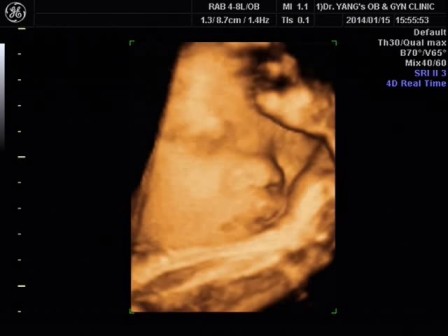

完成胎動檢查後,照超聲波,哈哈,肯好還可以看到少少泡菜BB的面部。醫生說泡菜BB各方面也很正常,泡菜BB體重2.9kg。^^